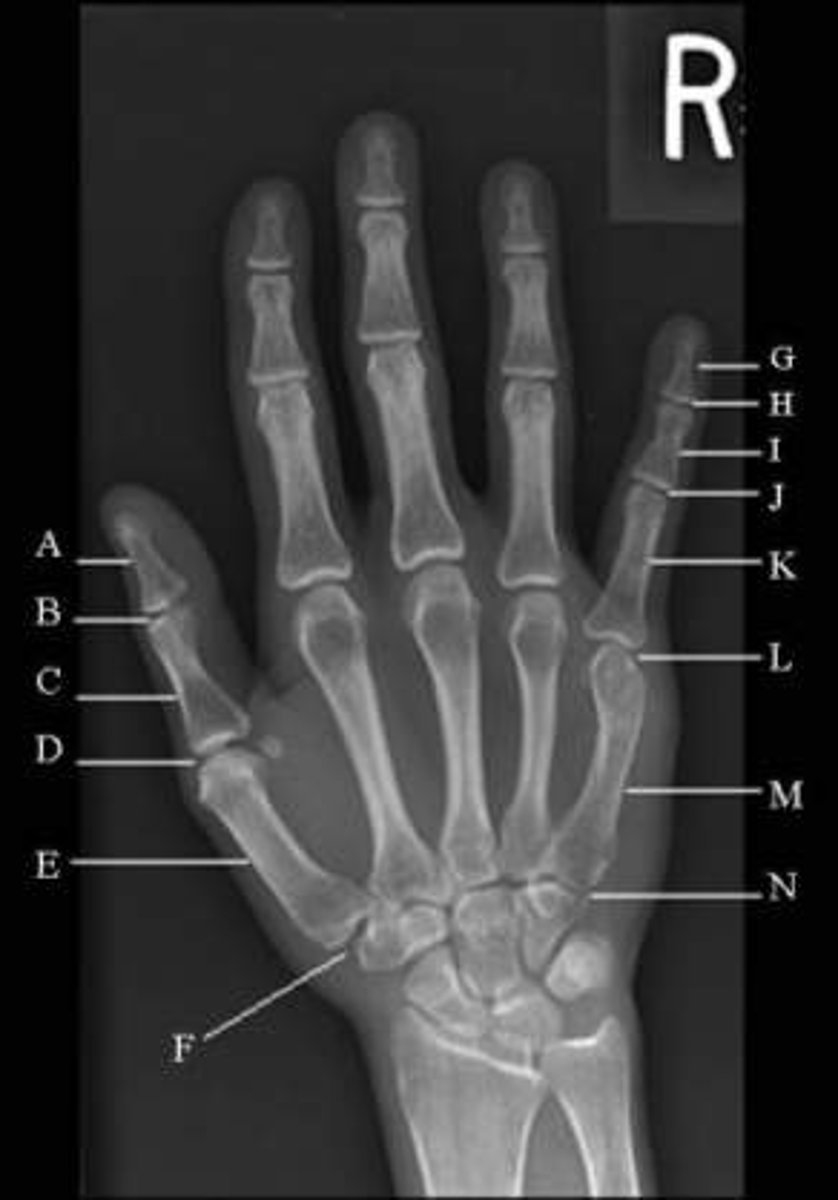

How many bones make up the phalanges of the hand?

14

How many bones make up the carpal region?

8

What is the total number of bones that make up the hand and wrist?

27

Which joint is between the two phalanges of the first digit (thumb)?

Interphalangeal Joint

Which joint is between the first metacarpal and the proximal phalanx of the thumb?

First Metacarpophalangeal

Which joint is between the middle and distal phalanges of the fourth digit?

Fourth Distal Interphalangeal

Which joint is between the carpals and the first metacarpal?

First Carpometacarpal

Which joint is between the forearm and the carpals?

Radiocarpal

Which joint is between the distal radius and ulna?

Distal Radialulnar